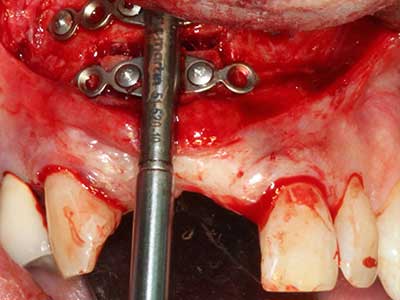

Si es preciso realizar intervenciones quirúrgicas en las que el hueso está en contacto directo con estructuras sensibles, como son los vasos sanguíneos o los nervios, los instrumentos rotativos presentan un enorme potencial de provocar lesiones iatrogénicas. Así, precisamente en la representación de nervios después de una lesión iatrogénica, o en el transcurso de la lateralización de un nervio para resecciones, reconstrucciones o incorporación de implantes, los equipos piezoeléctricos pueden resultar muy útiles para preparar la tapa ósea y retirar las partes de tejido duro cercanas al nervio (fig. 17-20). Por lo general, un ligero contacto del cordón nervioso con el inserto piezoeléctrico no tiene consecuencia alguna; ahora bien, un procedimiento poco cuidadoso con movimientos tipo sierra o piezas de trabajo sobre la base ósea aún existente puede provocar lesiones nerviosas temporales o incluso permanentes. Con todo, el riesgo de sufrir una lesión de este tipo se considera significativamente inferior que en los casos en los que se utilizan sierras y fresas (Pereira, Gealh et al. 2014).

El tejido óseo no solo tiene un contenido puramente mineral, sino que también presenta una importante proporción de fibras de colágeno. Esto no solo garantiza una buena resistencia a la presión, sino también una cierta flexibilidad, que puede aprovecharse para la realización de aumentos. En la plastia de expansión clásica a efectos de una partición ósea, la cresta maxilar atrofiada se divide en su eje longitudinal y, tras alcanzar una profundidad de osteotomía suficiente, se extiende con cuidado (fig. 13-16), en un caso ideal sin desperiostizar de forma visible el maxilar (Brugnami, Caiazzo et al. 2014, Stricker, Fleiner et al. 2014). Los sistemas de tornillos y placas con distancia de expansión creciente han demostrado su eficacia para distanciar entre sí las dos tablas óseas por debajo del umbral de rotura. Por regla general, se requieren anchuras de hueso residual de al menos 3 a 4 mm (Chiapasco, Zaniboni et al. 2006) para garantizar una flexibilidad y una cobertura ósea suficientes de los implantes que van a incorporarse. En caso necesario, una osteotomía de descarga vertical unilateral o bilateral puede mejorar la flexibilidad. Como alternativa a la técnica clásica se ha descrito una combinación con otras técnicas de aumento, sobre todo en la parte bucal.

Con el uso de sierras piezoeléctricas la división se efectúa de forma especialmente cuidadosa y sin pérdidas importantes de las dimensiones, por lo que no se han encontrado diferencias significativas entre los implantes realizados en el maxilar dividido y en la cresta alveolar no deficitaria (Chiapasco, Zaniboni et al. 2006, Danza, Guidi et al. 2009). No obstante, precisamente en la partición profunda y limitada de forma local, es preciso asegurarse de que exista una adecuada irrigación por agua para evitar que se produzcan sobrecargas térmicas en las áreas de osteotomía apical.